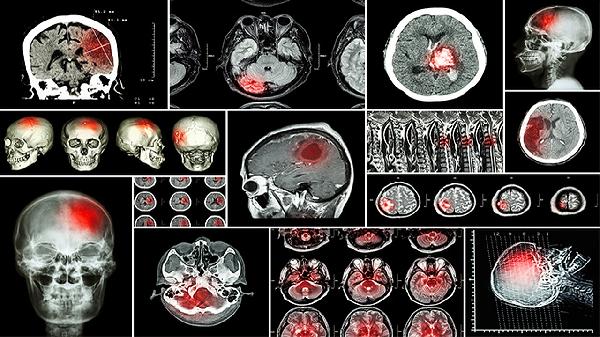

我今年52岁,2018年3月7号做CT检查右侧侧脑室后角可见类圆形短T1长T2信号,大小约0.5CMX0.5CM,DWI呈高信号怎么办呢

你说这个情况是右边的,老式发生了上述脂肪瘤,这个肯定是需要通过手术修复治疗的药物治疗基本上效果就不是很好,这个需要知道,平时注意观察和休息,目前发生的表现,只能是通过营养支持手术治疗也要告诉我有没有压迫血管神经的话会有这个症状表现。

患者主要是颅脑磁共振检查发现侧脑室后角脂肪瘤的情况,那么对于上述情况来说,假如还能手术治疗的前提下,可以考虑手术治疗。不过这个仅仅是我个人的看法,绝对不敢代表百分之百正确,仅供您参考,还请您以接诊医生实际诊疗的意见为准了。